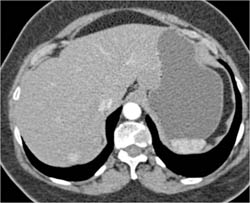

Diagnosis

GIST Tumor